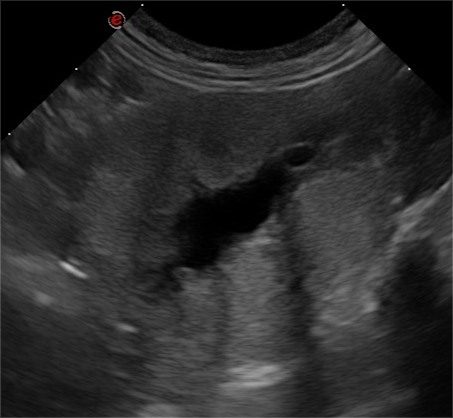

An advanced, highly practical ultrasound course designed to extend diagnostic capability, combining hands-on training in challenging abdominal structures, Doppler techniques and ultrasound-guided sampling for confident clinical application.

This course is suitable for you if you‘re a general practitioner who already has experience performing an abdominal ultrasound and would like to elevate your skills in evaluating the more challenging abdominal structures and at performing ultrasound-guided sampling. You’ll also learn how to use ultrasound for the assessment of the thorax (except heart) and neck, increasing the range of applications of this imaging modality that you can offer your patients. This two day Advanced Small Animal Ultrasound course will consist of a combination of lectures and several hands on practical sessions with the guidance of the course tutors.

- Introduction to Doppler techniques and the identification of portosystemic shunts with ultrasound